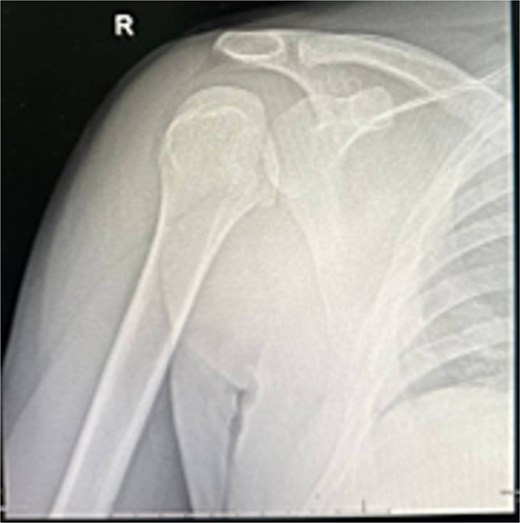

At 2 weeks, the wound healed well, and rehabilitation began at 4 weeks. At 6 weeks, he achieved 120° forward flexion, 160° abduction, and improved external rotation. At 2 months, flexion increased to 140°, abduction to 170°. By 6 months, he reached 160° flexion, 170° abduction, with minimal external/internal rotation lag (Figs 4–6).